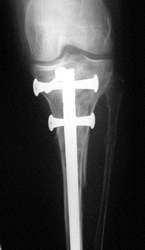

"SCN-Nagel bei Tibiafraktur"